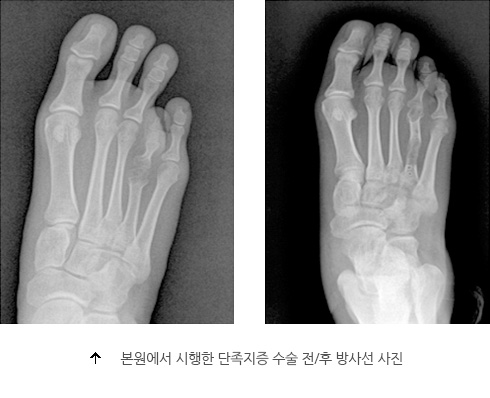

단중족증은 선천적으로 중족골의 발육에 이상이 발생해서 발가락이 짧아지는 기형입니다. 주로 4번째 발가락에서 흔히 볼 수 있고 종종 양측에서 대칭적으로 나타나는 특징이 있습니다.

치료는 수술로써 짧아진 중족골을 다른 발가락과 비슷한 정도로 늘려주는 수술을 하게 됩니다. 수술 방법은 외고정 장치로 조금씩 늘려주는 방법을 많이 이용합니다.